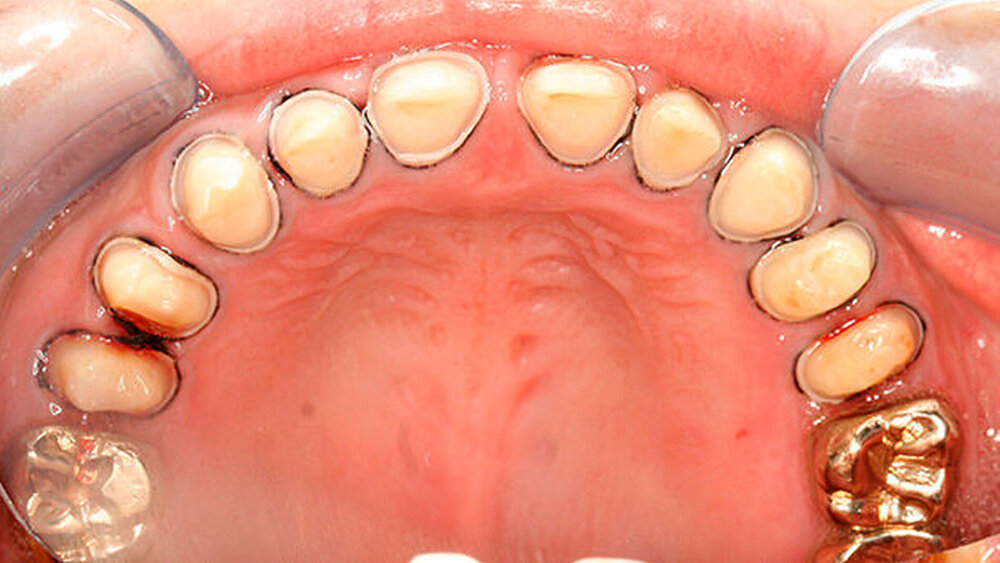

Bisher war die Patientin größtenteils mit provisorischen Maßnahmen behandelt worden. Eine Ausnahme bildeten hier die Sechsjahrmolaren, die ihrzufolge sehr zeitnah nach vollständigem Durchbruch mit Goldteil- beziehungsweise -vollkronen versorgt wurden. Im Oberkiefer wurden später auch für die zweiten bleibenden Molaren Vollkronen gewählt (Abbildungen 1 und 2).

Abbildung 1 gibt einen guten Überblick darüber, dass teils mehrere Restaurationen pro Zahn durchgeführt wurden und die dazwischen verbliebenen Bereiche aus Zahnschmelz oft nur gering waren (insbesondere an den Frontzähnen). Gleichzeitig zeigt aber auch der Vergleich der kontralateralen Prämolaren, wie anfällig dieser verbliebene Schmelz für Abplatzungen war. Im Unterkiefer ist gerade an Zahn 37 deutlich zu erkennen, wie großflächig die Schmelzverluste sein können, wenn auch die Restauration nicht mehr intakt oder vorhanden ist.

a) Dentinogenesis imperfecta. Da alle Zähne betroffen sind, ist von einer genetisch bedingten Fehlbildung auszugehen. Die Zähne der Patientin weisen zudem eine veränderte Farbe auf. Darüber hinaus sind Abplatzungen des Schmelzes vorzufinden. Trotzdem liegt keine Dentinogenesis imperfecta vor. Die Abplatzungen sind größtenteils geringfügig und zunächst oberflächlich, das heißt nicht unmittelbar bis zum Dentin. Die Farbänderung der Zähne entspricht nicht dem klassischen Bild einer Dentinogenesis imperfecta (siehe auch Abbildungen 3 und 4).

Zudem kann es immer wieder zu Abplatzungen des verbliebenen Schmelzes kommen, so dass der entsprechende Zahn eine neue Restauration benötigt, oder die schon vorhandene ausgedehnt werden muss (siehe auch Abbildungen 1 bis 3) [Crawford et al., 2007].